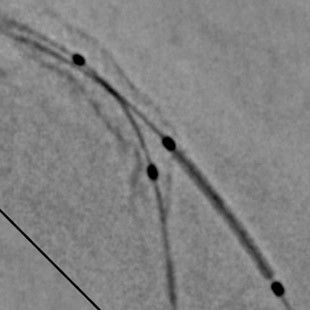

PCI ASSIST1 helps improve the image quality even in the most complex cases, at no extra X-Ray dose. For complex PCI procedures, such as bifurcations, PCI ASSIST helps to increase accuracy of stent placement, therefore reducing risks of MACEs such as restenosis and thrombosis. PCI ASSIST can help physicians increase their activity expanding to more complex procedures with confidence, opening also to novel generation of stents such as BVS.

PCI ASSIST helps improve visibility3 up to +85% in moving anatomy, and up to 75% in larger patients, at the same dose.